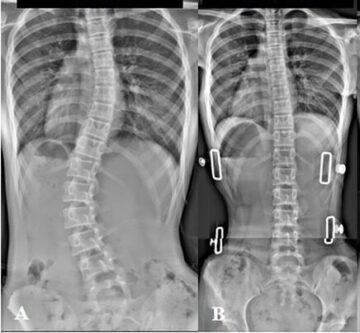

مارس 31, 2026 متى يجب علاج اعوجاج العمود الفقري البسيط مجهول السبب؟ قبل فوات الاوان… scoliosis, اعوجاج العمود الفقري, الجنف لا يوجد تعليق 38 المشاهدات متى يجب علاج اعوجاج العمود الفقري البسيط مجهول السبب؟ قبل فوات الاوان يشعر الكثير من الأهل بالقلق بعد تشخيص طفلهم بـ اعوجاج العمود الفقري البسيط المجهول السبب، ويتساءلون: متى يجب التدخل؟ وهل العلاج المبكر